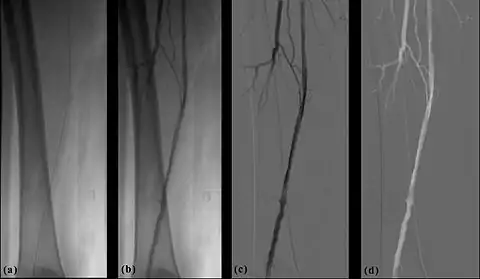

- The temporal-averaging feature of digital noise reduction can also be used for image presentation purposes so that the time course of the movement of contrast medium during a study can be displayed using just one image - see an example in Figure 7.4 from the peripheral study shown above - instead of a sequence of numerous images. Such an image is sometimes referred to as a Vascular Trace.

- One method of temporal filtration, referred to as Integrated Mask-Mode DSA involves adding (also called integrating) a number of images, acquired prior to the arrival of the contrast medium, to form an integrated mask image and adding a number of peak-opacification images to form an integrated live image. This is the process that was used to generate the vascular trace image in Figure 7.4. Thus, when four images are used to generate each integrated mask and live images, eight of the 25 images are now used in the subtraction process and, as a result, only 68% of the dose is wasted, and a subtraction image with lower noise results.

- A second method of temporal filtration, referred to as Matched Filtration, attempts to utilise all 25 images. It involves using information derived from the temporal variation in the concentration of contrast medium in the blood vessel of interest. This information can be obtained by using densitometric analysis software to plot the dilution curve for a region of the blood vessel, i.e. a plot of the time course of the contrast medium. This dilution curve is then used to define a range of weighting factors that are applied to each image in the sequence and the resulting images are simply added together. The processed DSA image has a relatively high SNR as a result of the integration of images. Further refinement of such filters can be used to colour-code parameters such as the time-of-arrival and the time-to-peak opacification, into the displayed image data. Although Matched Filtration has been shown both theoretically and experimentally to generate a DSA imaging process with good image quality and dose utilisation characteristics[27], it has not gained widespread clinical application.